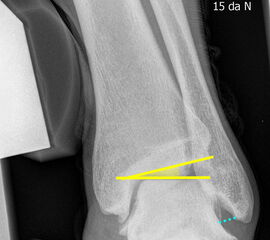

Böhler-Winkel (Syn. Tubergelenkwinkel)

Es wird eine Linie vom Proc. ant. calcanei zur dorsalen Facette des Subtalargelenks gezogen (rot). Die zweite Linie verläuft von der kranialen Begrenzung des Tuber calcanei zum Subtalargelenk (gelb). Gemessen wird der nach dorsal offene Winkel zwischen den beiden Linien (Norm: 22-48° 9).